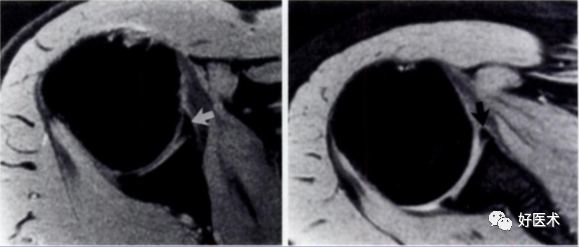

1.Bankart lesion

盂肱下韧带和前盂唇(前下盂唇韧带复合体)从关节盂边缘撕脱,伴肩胛骨骨膜的撕裂。首次损伤后不恰当愈合可导致反复肩关节不稳。

3.Perthes lesion

Bankart lesion的变异:前下盂唇韧带复合体从关节盂边缘脱离,但骨膜完整且向前内侧剥脱,因此盂唇可在正常解剖位置。

多见于反复脱位的患者。类似于Bankart 损伤,但其肩胛骨前骨膜保持完整,MR 关节造影显示对比剂出现于盂唇与肩胛骨关节盂之间,而骨膜完整连于肩胛盂 。

需与关节盂唇的变异鉴别。